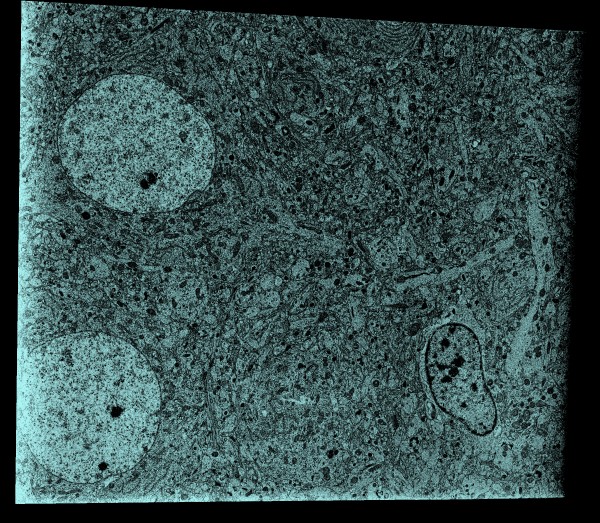

| Electron microscopy, serial block face

| Rat cortex plane

vol #503 planes z,1000,1500

| Synapse tomography

- Show serial block face em of rat cortex.

- Show tomography of synapse.